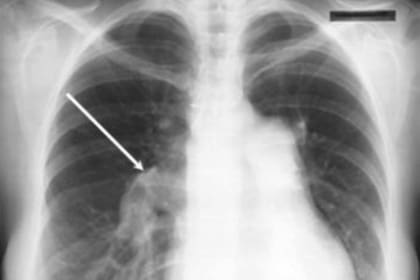

"Se trata de un trastorno en el cual la presión de las arterias y/o venas pulmonares se encuentra en niveles por encima de los normales [presión media de arteria pulmonar mayor de 25 mm de Hg en reposo, o mayor de 30 mm de Hg con ejercicio], lo que provoca que el lado derecho del corazón aumente su esfuerzo para hacer circular la sangre, causando en el paciente un cuadro conocido como insuficiencia cardíaca, y en casi todos los casos provocándole la muerte", explicó a LA NACION el doctor Julio Sandoval, especialista en hipertensión pulmonar e investigador del Instituto Nacional de Cardiología de México.

Según el profesional, la proliferación de células de forma descontrolada en el pulmón comienza a taponar esos vasos sanguíneos pulmonares que llevan la sangre sin oxígeno desde el ventrículo derecho a los pulmones para ser oxigenada. Cuando estas pequeñas arterias se estrechan, no pueden transportar mucha sangre, por lo que la presión se acumula y se genera una hipertensión pulmonar. El corazón necesita trabajar más fuertemente para forzar la circulación de la sangre a través de los vasos en contra de esta presión, lo que provoca con el tiempo que el lado derecho del corazón se vuelva más grande.